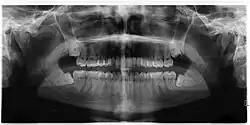

Impacted wisdom teeth are classified by their direction of impaction, their depth compared to the biting surface of adjacent teeth and the amount of the tooth's crown that extends through gum tissue or bone. Impacted wisdom teeth can also be classified by the presence or absence of symptoms and disease. Screening for the presence of wisdom teeth often begins in late adolescence when a partially developed tooth may become impacted. Screening commonly includes a clinical examination as well as x-rays such as panoramic radiographs.

If the tooth cannot be assessed with clinical exam alone, the diagnosis is made using either a panoramic radiograph or cone-beam CT. Where unerupted wisdom teeth still have eruption potential several predictors are used to determine the chance of the teeth becoming impacted. The ratio of space between the tooth crown length and the amount of space available, the angle of the teeth compared to the other teeth are the two most commonly used predictors, with the space ratio being the most accurate. Despite the capacity for movement into early adulthood, the likelihood that the tooth will become impacted can be predicted when the ratio of space available to the length of the crown of the tooth is under 1.[5]: 141

There is no standard to screen for wisdom teeth. It has been suggested, absent evidence to support routinely retaining or removing wisdom teeth, that evaluation with panoramic radiograph, starting between the ages of 16 and 25 be completed every 3 years. Once there is the possibility of the teeth developing disease, then a discussion about the operative risks versus long-term risk of retention with an oral and maxillofacial surgeon or other clinician trained to evaluate wisdom teeth is recommended. These recommendations are based on expert opinion level evidence.[19] Screening at a younger age may be required if the second molars (the "12-year molars") fail to erupt as ectopic positioning of the wisdom teeth can prevent their eruption. Radiographs can be avoided if the majority of the tooth is visible in the mouth.